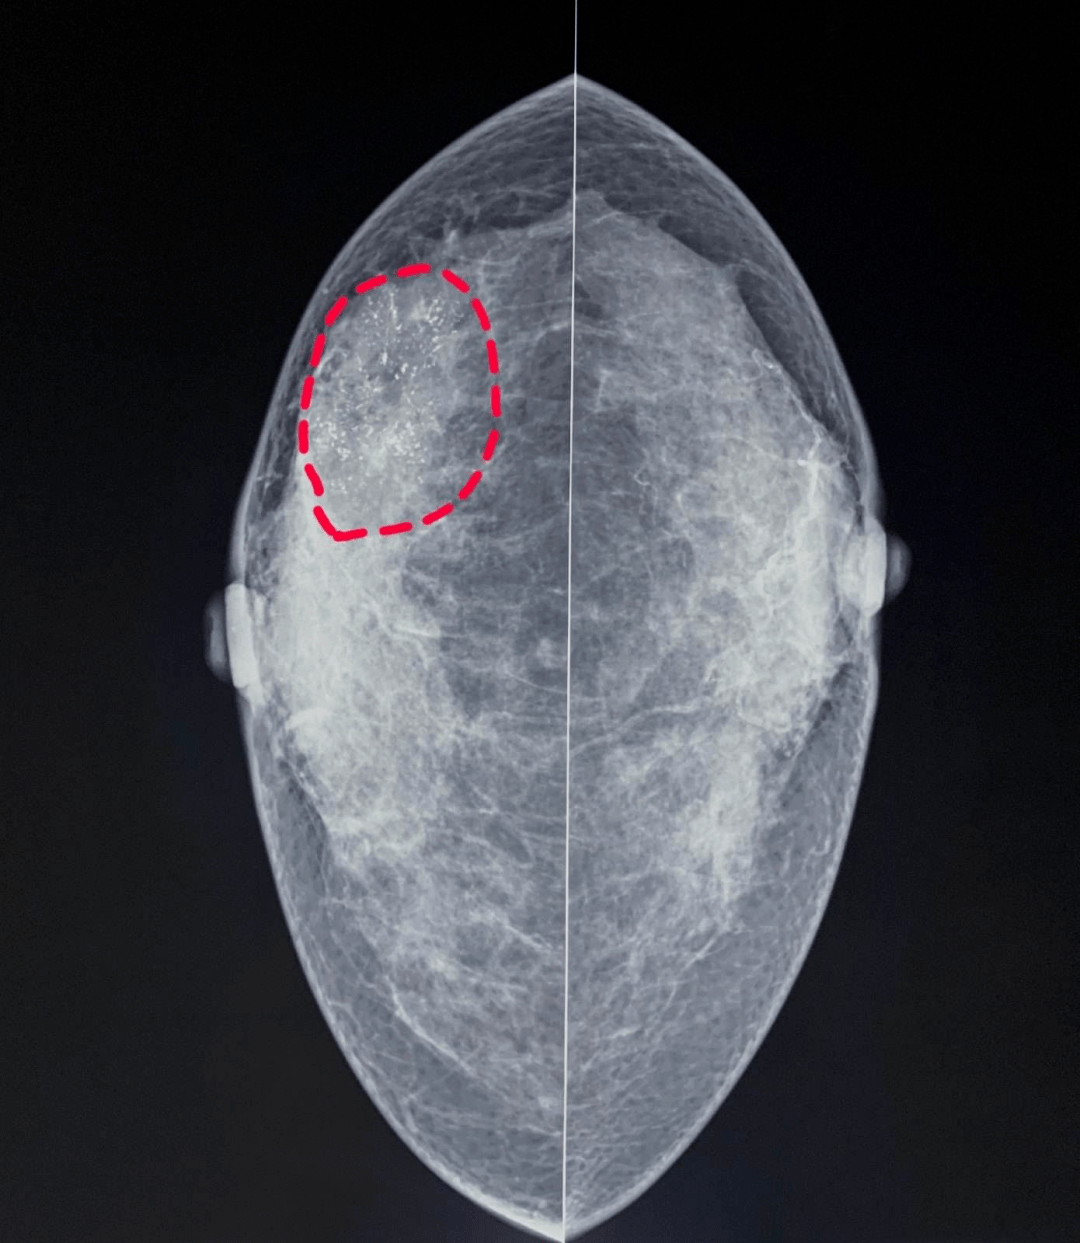

这个右侧有很多钙化灶也是一些早期这个是右边乳腺有密集的钙化灶